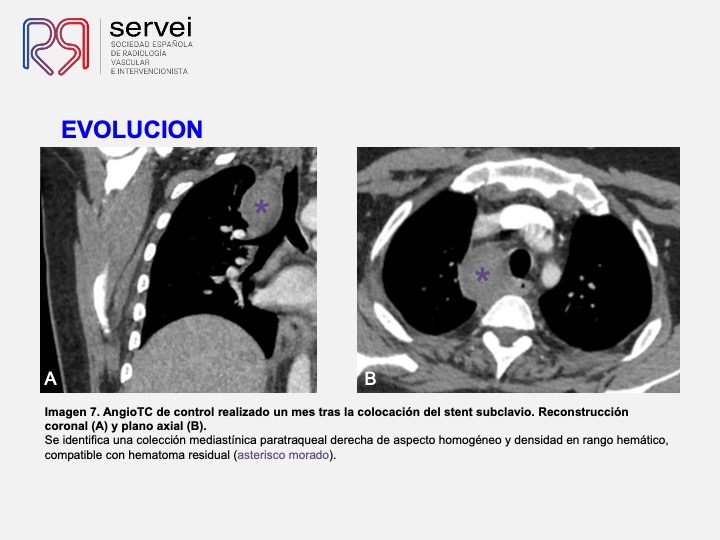

Pseudoaneurismas de la arteria subclavia tras intento de canulación de ECMO yugulo-femoral. Tratamiento con stent cubierto